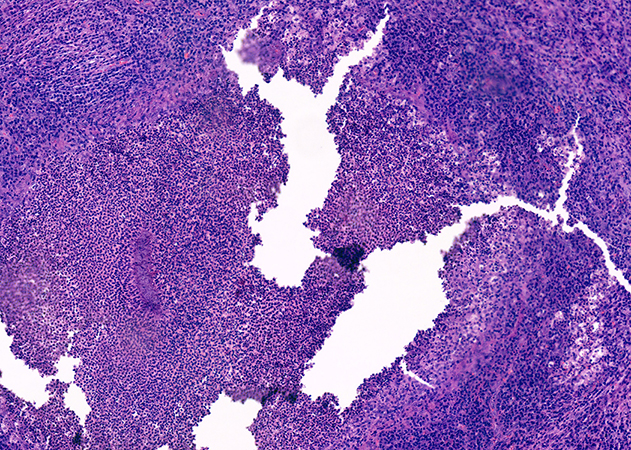

The submitted material consisted of fragments of lung parenchyma with firm consistency and poorly defined whitish-yellow areas. No evident tumor masses were identified. The intraoperative study (Figure 1) showed chronic suppurative inflammation with abundant infiltrate of neutrophils, lymphocytes, and plasma cells, associated with areas of necrosis and microabscesses. In the subsequent deferred study, rounded basophilic granules were identified, consisting of bacterial colonies with a central filamentous arrangement and a peripheral eosinophilic halo (Splendore-Hoeppli phenomenon) (Figures 2 and 3). Gram staining revealed Gram-positive filamentous bacilli (Figure 4). Grocott staining was positive (Figure 5), highlighting filamentous structures. Ziehl-Neelsen staining was negative (Figure 6).